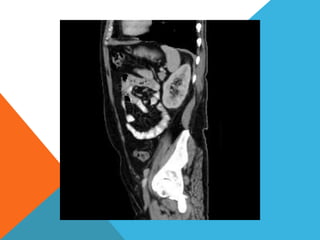

El paciente presentó síntomas de sangrado digestivo y pérdida de peso. Exámenes revelaron gastritis crónica asociada a H. pylori. Un tumor fue descubierto en una colonoscopia normal. La cirugía removió un tumor fibroide solitario, una rara neoplasia mesenquimal que usualmente crece lento y tiene bajo potencial de malignidad. El pronóstico después de la remoción quirúrgica es generalmente bueno.